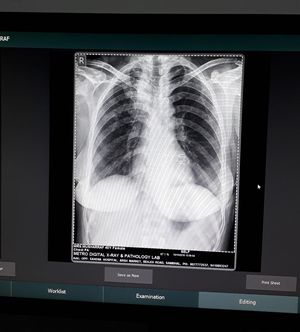

Chest xray PA view

A lady of 40 year old history of falling down and injury in right lateral side of thorax and severe pain.. Difficulty in breathing and swallow..

See the dilated esophagus.